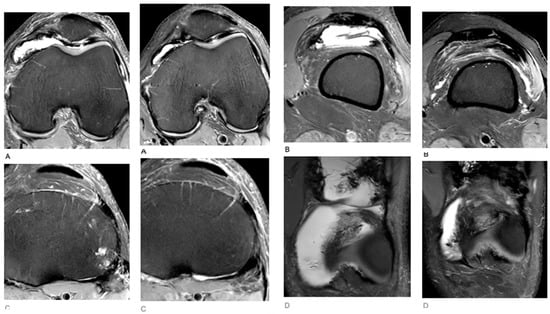

2. Case Presentation

3. Results